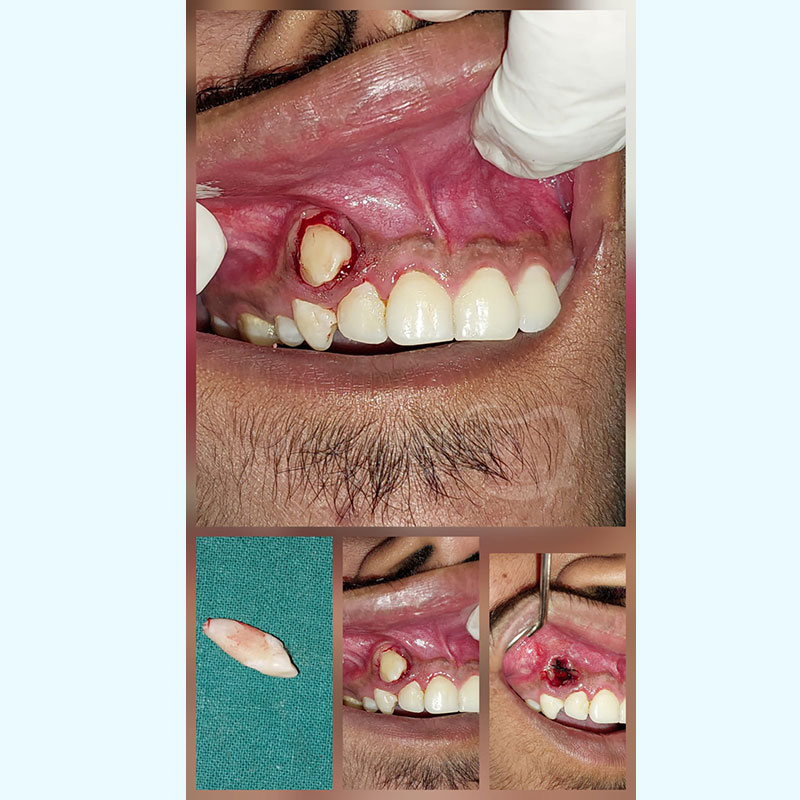

Extraction Of Labially Placed Canine